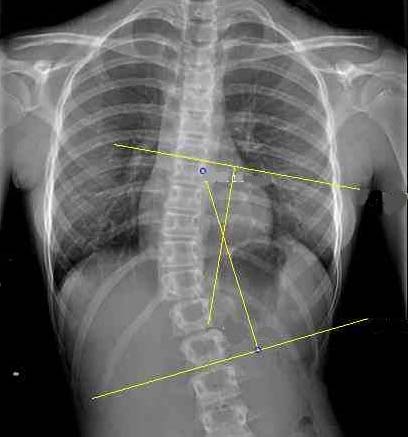

The Cobb angle is calculated drawing firstly two parallel lines tangential the two must tilted vertebrae above and below the curve’s apex and, secondly, two perpendicular lines crossing the tangential ones. The angle is measured at the intersection of the perpendiculars. The inclinometer helps quickly identifying the most tilted vertebrae on radiographs.

On traditional radiographs, the Cobb angle can be drawn using ruler and pencil and measured with a goniometer. The inclinometer can ease the measurement simply placing the tool at the spine’s most tilted vertebra above and beneath the curve’s apex and adding their angle of inclination together.

If radiographs are seen on the computer, the Cobb angle is measured adding together the angles of inclination of the two most tilted vertebrae above and beneath the apex with respect to the horizontal line and using the tools available on the disk (see image).

If the vertebral edge cannot be clearly identified, the tangent to the pedicle is considered the reference point.